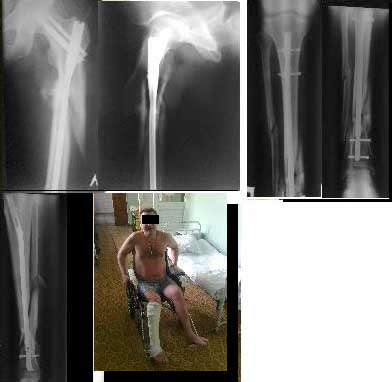

Спасибо уважаемому Джолдасу за ссылку на мою грешную личность. Мое мнение следующее. Уважаемый Сергей! Если Вы хорошо владеете методом чрескостного остеосинтеза, то можете приступать к делу не задумываясь. На рентгеновских снимках созерцаю картину, из которой можно получить наилучший результат именно внешним остеосинтезом. Слова типа "собирать аппарат нудно и т.п", наверное, не совсем к месту. Подарите человеку полное здоровье и, как говорил ныне покойный Леонид Ильич, Вы получите чувство глубокого удовлетворения. И уважения. В данном случае травматичные методы вмешательства могут весьма негативно сказаться на и так подорванных остеогенных потенциях тканей и иметь непредсказуемые последствия. А еще лучше - пришлите пациента к нам в Курган. Обещаем выставить результаты лечения на всеобщее обозрение.

Выставляю случай не менее тяжелый. Фиксация в аппарате Мацукидиса-Шевцова 83 дня, общий срок нетрудоспособности 112 дней. Никаких проблем с остеосинтезом и с последующим лечением не было. Никаких воспалений мягких тканей. 3 перевязки за весь период лечения.Главное - захотеть.

5.10.2011 синтез правой голени стержнем Деост, в закрытую с применением дистрактора и остеотомией малоберцовой кости. Снимки в приложении. Пациент активизирован, начал передвигаться на коляске, сегодня встал с костылями.

Картинки мелковаты. Голень вроде совсем красиво получилась. Бедро - центральный отломок остался в сгибании. Будем надеяться, это не будет проблемой, и срастется так.